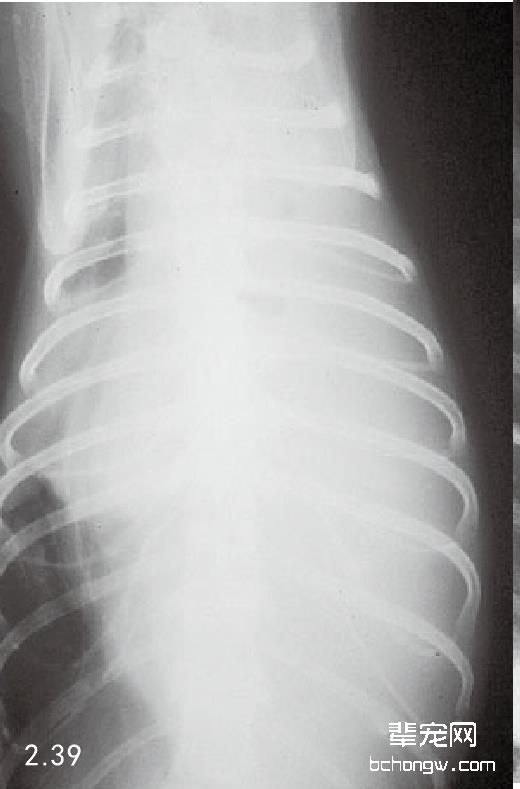

图2.39 猫患单侧脓胸而影响左半胸的背腹侧胸腔X线片。